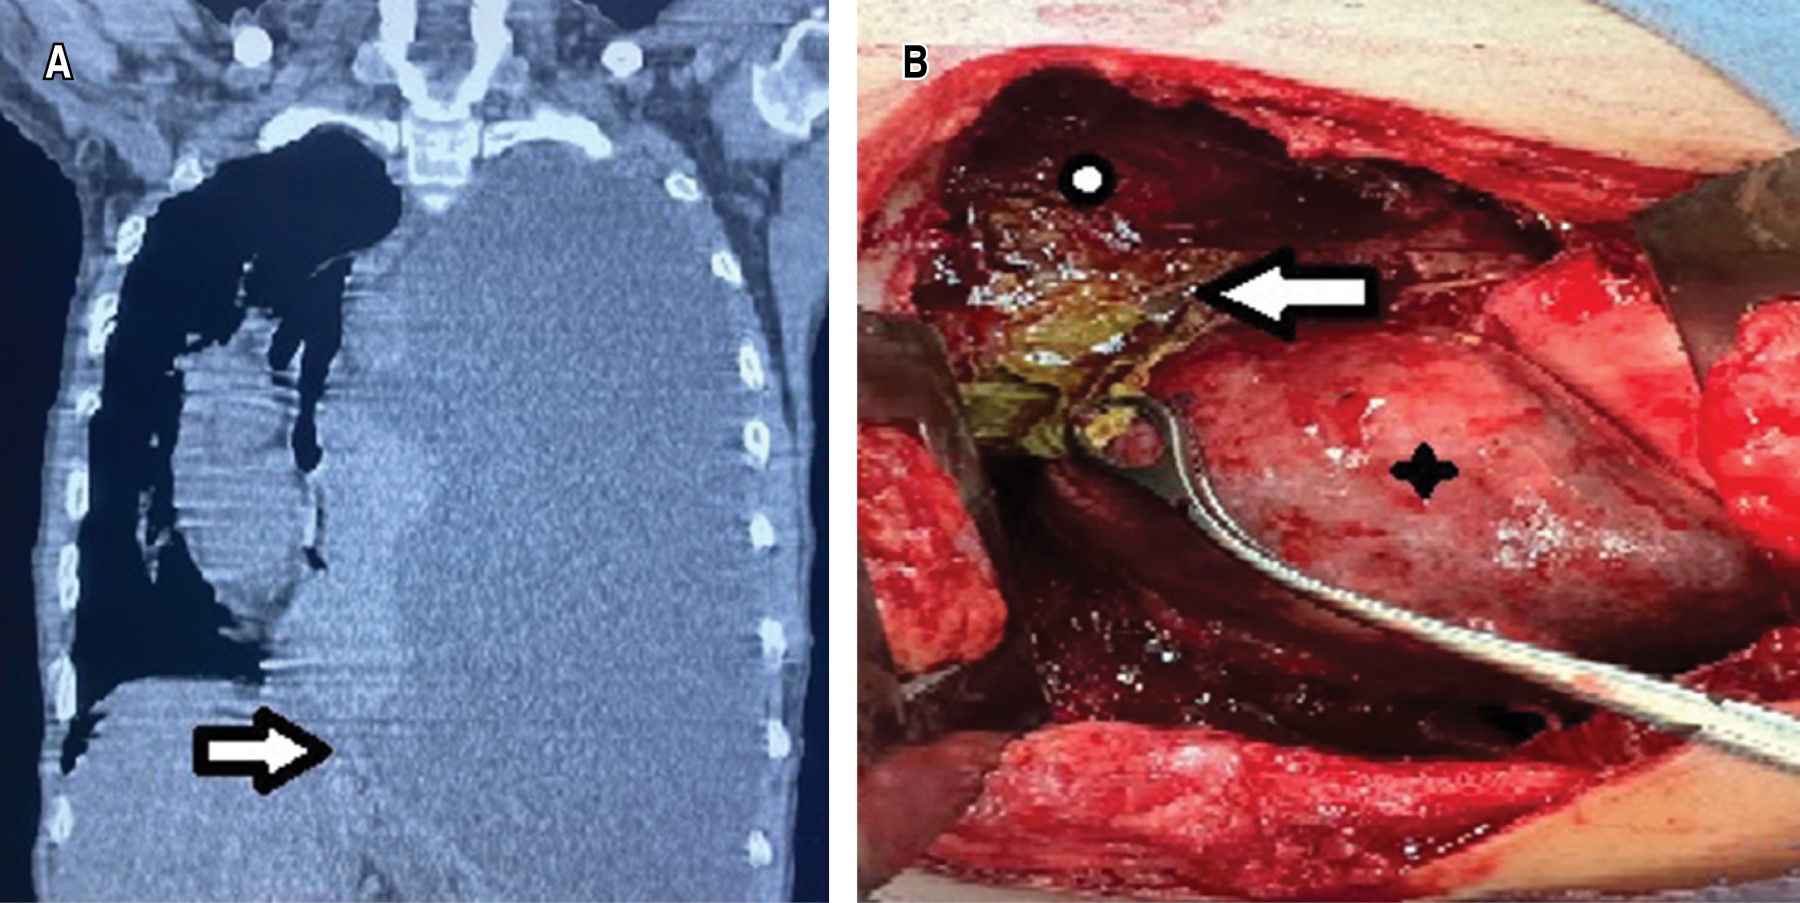

Caso clínico 1. Hombre de 39 años, con antecedente de alcoholismo crónico, con episodios de dolor abdominal recurrente. Inició su padecimiento tres meses previos a su ingreso, con dolor pleurítico en hemitórax izquierdo, se agregó disnea progresiva y ataque al estado general; se tomó radiografía de tórax en la cual se identificó derrame pleural. Se realizó toracocentesis y se obtuvo líquido pleural de aspecto oscuro, espeso; mismo que, al análisis citológico y citoquímico, presentó cifras de amilasa en 16,043 U/L y con criterios de Light de exudado neutrofílico. Posteriormente, al realizar tomografía axial computarizada (TAC) de tórax y abdomen (Figura 1A), se identificó comunicación de líquido libre del abdomen con el hemitórax izquierdo, por lo que se decidió llevar al paciente a la sala de quirófano para realizar toracotomía posterolateral; se encuentra pleura parietal con grosor de 8 mm y visceral de 5 mm, abundante material de fibrina y pus en cavidad, un trayecto fistuloso entre la cavidad abdominal y diafragma izquierdo de 1 cm de diámetro (Figura 1B), con colección de 100 mL de líquido blanquecino. Se realizó lavado y decorticación hasta lograr adecuada expansión pulmonar, el trayecto fistuloso se desbridó; se identificaron bordes y se realizó cierre del defecto con sutura no absorbible de polipropileno 2/0 (Figura 1C); se verificó reexpansión pulmonar. Posterior al tratamiento, el paciente cursó con adecuada evolución clínica; los drenajes endopleurales, con gasto serohemático que disminuyó hasta su retiro cinco días después del procedimiento. Se realizó TAC de control, la cual mostró disminución de la colección pancreática inicial. Después de valoración por el Servicio de Gastroenterología, se dejó manejo conservador. A los seis meses de vigilancia con TAC de tórax, sin evidencia de complicaciones.

Caso clínico 2. Hombre de 27 años, en sus antecedentes destaca alcoholismo desde los 14 años y episodios de dolor abdominal presentados desde un año previo a la valoración, por lo que acude a atención hospitalaria. Refiere disnea progresiva además de aumento del dolor abdominal, a lo que se agrega dolor torácico. Se le realizó TAC de tórax que reportó ocupación de hemitórax izquierdo asociado a derrame pleural masivo, con desplazamiento a la derecha de estructuras mediastinales (Figura 2A). Se colocó sonda endopleural izquierda, la cual, tras la colocación, persiste con gasto de aproximadamente 600 mL diarios durante dos semanas, de aspecto oscuro de consistencia líquida. Continúa con deterioro respiratorio, por lo que es referido al Área de Cirugía de Tórax donde solicitan análisis del líquido pleural, el cual revela exudado hemático con niveles elevados de amilasa (195 U/L) y lipasa (3,095 U/L). Además, mostraba leucocitosis y trombocitosis en reporte de biometría hemática. Se complementa con TAC de abdomen y se identifica colección abdominal peripancreática que corresponde con pseudoquiste pancreático. Se decide pasar a quirófano; se realiza lavado y decorticación izquierda; se identifica derrame pleural secundario a pseudoquiste pancreático comunicado a hemitórax izquierdo a través del hiato esofágico, atrapamiento pulmonar, derrame pleural septado y fibrotórax izquierdo (Figura 2B). En el posoperatorio, los drenajes pleurales produjeron bajo gasto, de aspecto serohemático (30-100 mL/día); son retirados al día cinco y siete del posquirúrgico. Se realizó TAC de control donde persiste colección abdominal mínima. Posterior a valoración por el Servicio de Gastroenterología, se decide mantener conducta expectante. El paciente cursó con buena evolución posquirúrgica y fue dado de alta en el día 10 del posoperatorio. En seguimiento posquirúrgico, al mes y a los tres meses con radiografía simple de tórax y a los seis meses con TAC de tórax, no presenta evidencia de complicaciones.